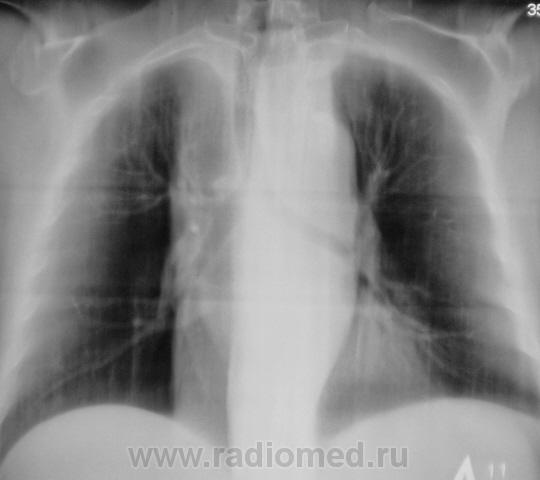

А на ЛГМ не похоже?

Ну конечно, все правильно, при нео верхнего средостения - думаем о ЛГМ...

Пациент взят, на контроль, а это значит, что он полностью "голый" - ни анализов, ни осмотра, ни....чего.

Ну, что-т о написать все одно надо. На мой взгляд скиалогия ЛГМ ближе. Слово за биопсией

С тех пор в закл. выношу - образование средостения...